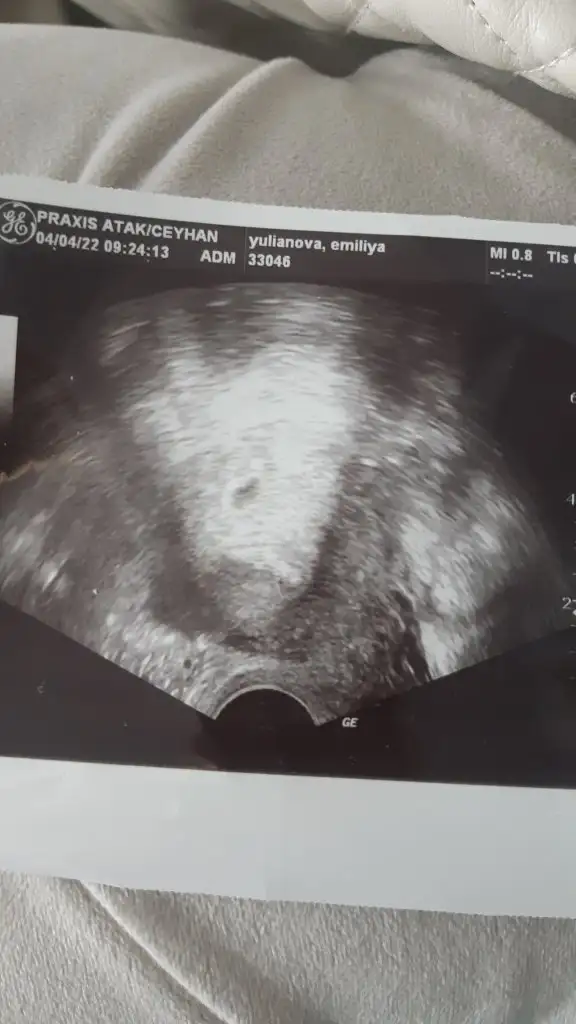

Bana da yorum yapabilir mısınız acaba 7+1 vajinal

Eklentiler

• 16431973968671822837059084314472.webp

11,6 KB · Görüntüleme: 91